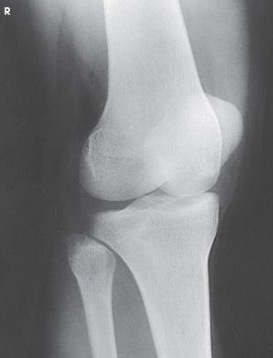

What Knee projections is this

AP Knee

Patient position for AP Knee

supine, no pelvic rotation

In AP Knee, the femoral epicondyles are what to the IR

parallel

The CR in Knee projections are variable depending on the what

ASIS

If Patient’s ASIS is less than 19cm from the table, then the CR angling would be

3 to 5 degrees caudal

If Patient’s ASIS is more than 24cm from the table, then the CR angling would be

3 to 5 degrees cephalic

If Patient’s ASIS measures 19 to 24cm from the table, then the CR angling would be

0 degrees

The CR in an AP knee enters

½ inch below pateller apex

Radiation field for AP Knee is

10 × 12 inch LW

The Patella superimposed on the femur (will

lie slightly to the medial side) is seen on